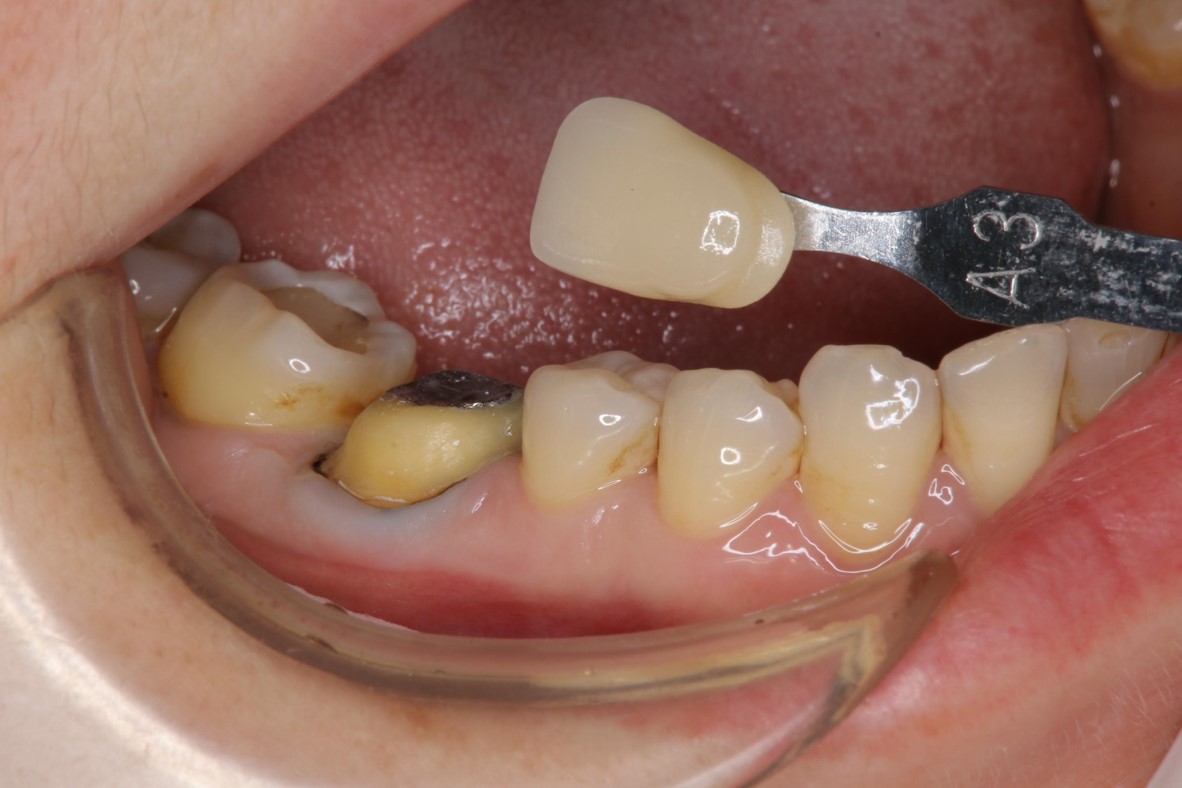

膺復前評估牙齦、牙齒狀態

照相比色